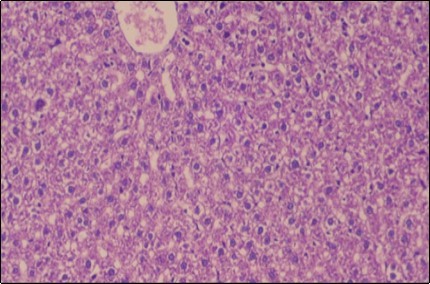

The histological examination of the livers of control rats feeding standard diet showed normal architecture hepatocytes, blood sinusoid and central vein, figure 6. The rats which were fed on a (HFD), showed swollen hepatocytes with vacuolated cytoplasm filled with fatty infiltration, congested central vein and disappearance of blood sinusoids, figure 7. By comparison, the liver of rats that were treated by fennel after obesity and control mice observed nearly normal of the hepatocytes with eosinophilic cytoplasm, central vein and clear blood sinusoids and more bi-nucleated cells, figure 8. While examination of rats' liver that were treated by Ator and after the obesity appears, they showed mild fatty change in hepatocytes, few hepatocytes retain is eosinophilic cytoplasm and central vein figure 9. Liver of rats that were treated by fennel and Ator after obesity and control rats are showing nearly normal hepatocytes figure 10.

Figure 8.Photomicrograph of liver section of treated rat with fennel herb showing nearly normal of the hepatocytes with eosinophilic cytoplasm, central vein (CV) and clear blood sinusoids and more bi-nucleated cells , (H&E) (40X).